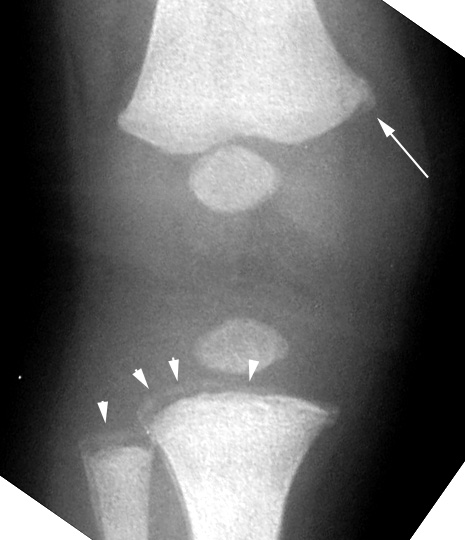

Tibia And Fibula: Arrowheads Point To Fracture That Runs Across

bucket handle fracture corner chip metaphyseal abuse child femur tibia pediatrics fridays distal above below arrowheads fibula runs appearance arrow

Femur: Metaphyseal Lipping Of Distal Femur - Corner Fracture

femur corner fracture metaphyseal distal abuse child lipping